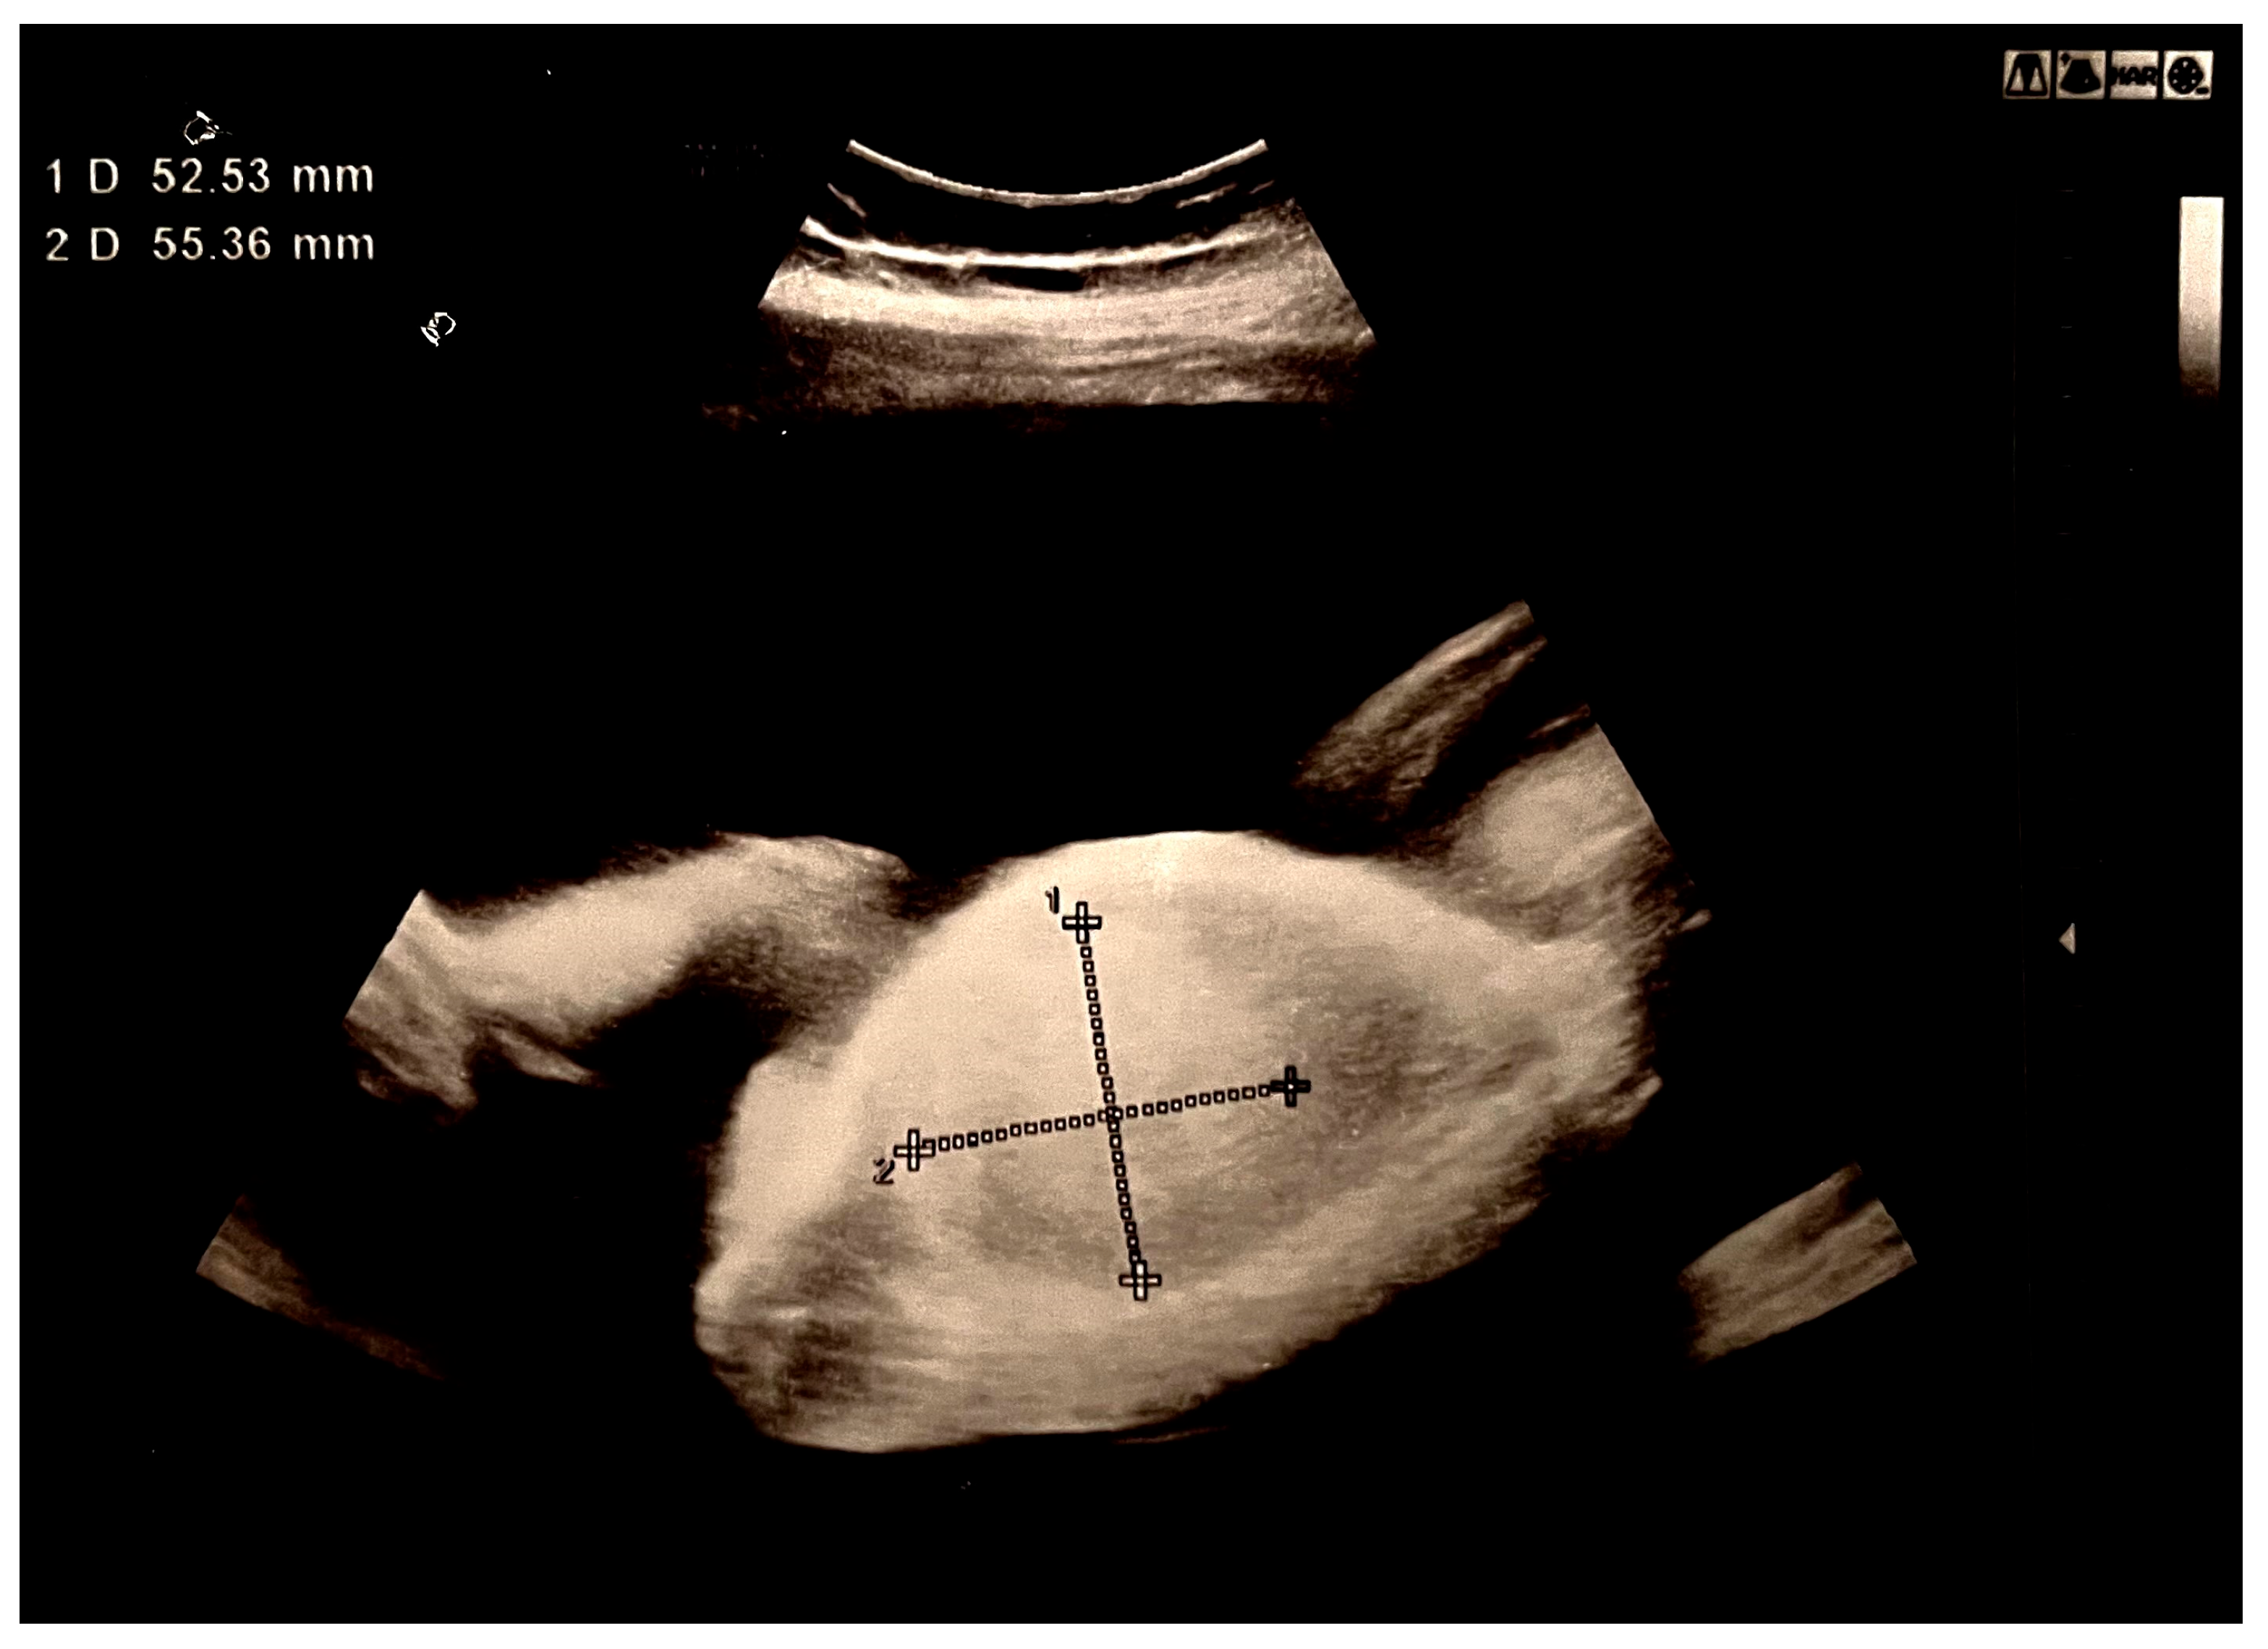

A 22-year-old female patient was admitted as an emergency case to the Clinic of Gynecology and Obstetrics at the University Clinical Center of Serbia in the 28th week of her first pregnancy, which was spontaneously conceived, due to a significantly increased amount of amniotic fluid. Initial ultrasound examination confirmed fetal vitality and appropriate fetal biometrics for gestational age, as well as an increased amount of amniotic fluid (Amniotic Fluid Index: 170 mm). A tumor-like hyperechoic formation in the fetal abdomen, measuring 52.53 × 55.36 mm, was noted but could not be reliably identified (Figure 1).

Figure 1. Hyperechoic tumor formation in the abdomen of the fetus, size 50 × 50 mm.